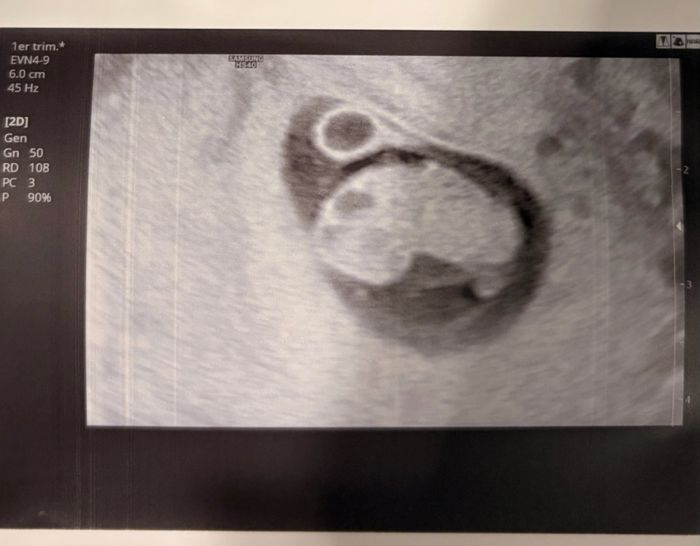

Hola. Sabrías decirme en esta transvaginal de 6+2 si es niño o niña? Gracias Smiley smileMétodo Ramzi 2